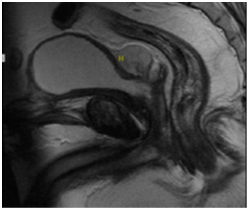

Figure 1 (a) CECT showing a large irregular polypodial heterogeneously enhancing mass lesion involving the base of the bladder with dimensions of 8.7(ML)x8(AP)x12.1(CC)cm3. Masslesion shows loss of fat plane with the bladder and involvement of the left VUJ. There is an exophytic component of about 4.1x4cm arising from the posterior wall as well. (b) Intraoperative images of enucleation of prostatic tumor. (c) 100X, H&E showing part of prostatic tumor with few enlarged blotchy nuclei in an overall hypercellular stroma. Part of prostatic urethral lining epithelium seen on the right.

Chemotherapy/Radical surgery was withheld due to lack of patient consent / unclear treatment protocols for the entity and the patient was kept on regular follow up with cystoscopy every 3 months. On his second follow up visit, there was evidence of a recurrence with a 1cm growth in prostatic urethra MRI showed a well-defined, homogeneous, T1 iso and T2, PD hyper intense lesion measuring 3.2x2.8x2.3cm is noted in the recto-vesical area in close relation to the urinary bladder and seminal vesicles with intense diffusion restriction. The lesion shows relatively homogeneous post contrast enhancement with few necrotic areas. Left aspect of proximal prostatic urethra shows a heterogeneously enhancing irregular hetero-intense lesion measuring 15x12mm, extending into the seminal vesicles. Peripheral zone of Prostate is visualized and appears normal in signal intensity (Figure 2). No significant iliac lymphadenopathy was noted. Re-resection was done and HPE again showed features of STUMP. Thus, there appears to be evidence of recurrence in the patient. The patient is able to attend to his routine work/activities as of now. Chemotherapy / surgery needs to be planned in view of the Sarcomatous change.

Figure 2 MRI showing a well-defined, homogeneous, T1 iso and T2, PD hyper intense lesion measuring 3.2x2.8x2.3cm3 in the recto-vesical area in close relation to the urinary bladder and seminal vesicles with intense diffusion restriction with relatively homogeneous post contrast enhancement and few necrotic areas.